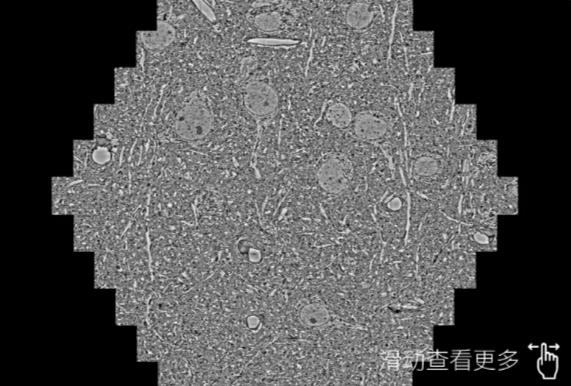

鼠脑切片。左图使用黔江蔡司黔江扫描电镜MultiSEM706对165μmx143pm面积区域成像,耗时仅需1.5秒。右图为鼠脑切片中30μm区域放大效果。样品由芝加哥大学B.Kasthuri提供。

使用蔡司高速黔江扫描电镜MultiSEM对1mm²人脑皮层组织进行高分辨成像,并对其中的各种细胞结构进行三维重构分析。左图展示了2x3mm²组织平面中锥体神经元的三维重构效果。右图显示了局部体积神经元三维重构。图像由哈佛大学chtman实验室提供,渲染图由D. Berger 制作。